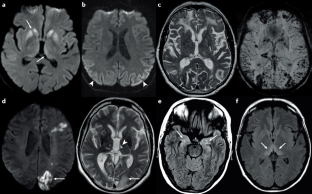

Vitali, P. et al. Diffusion-weighted MRI hyperintensity patterns differentiate CJD from other rapid dementias. Neurology 76, 1711–1719 (2011).